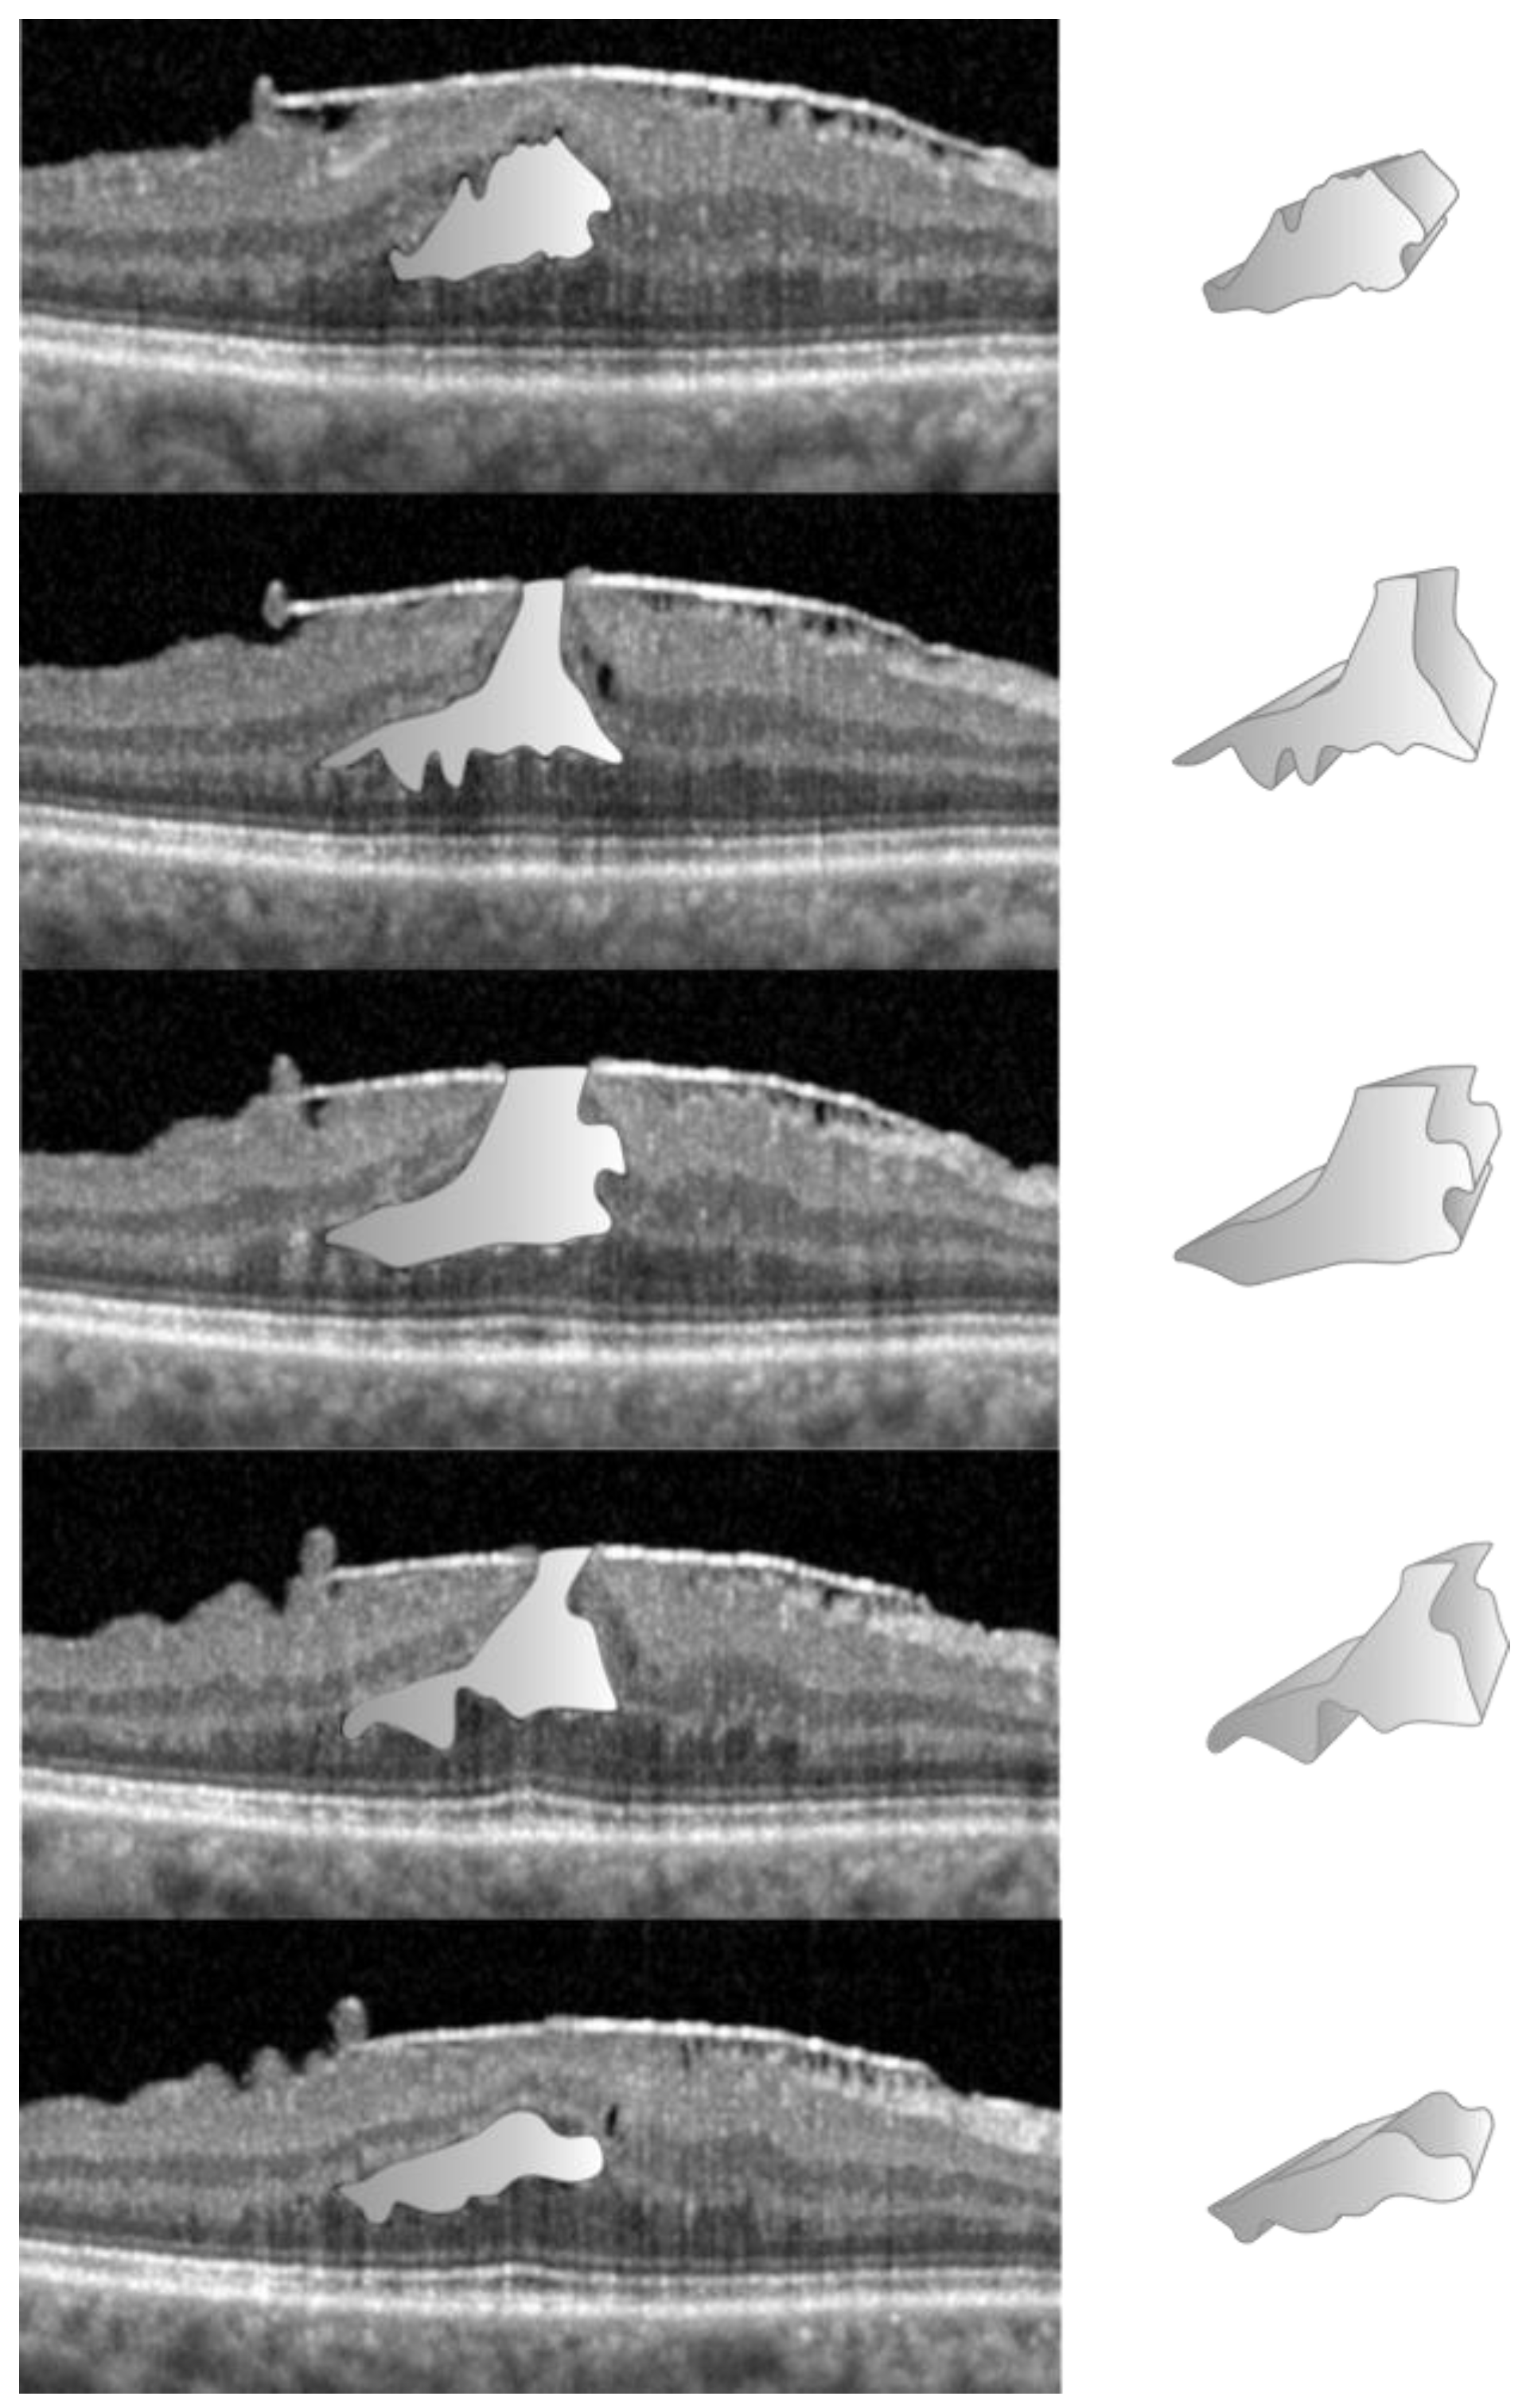

2. Materials and Methods

3. Results